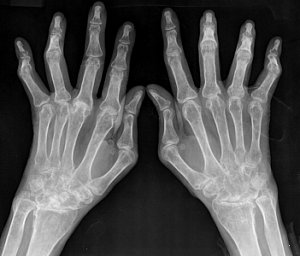

퇴행성관절염이 10~20년 동안에 걸쳐 서서히 진행되는 것과는 다르게 류마티스 관절염은 1~2년 안에 관절의 변형이 빠르게 나타난다. 그러므로 류마티스 관절염은 초기에 치료하여 증상이 번지지 않도록 관리해주는 것이 매우 중요하다.

초기에 발견했음에도 치료하지 않거나 발병 후에도 제 때 적절한 치료를 받지 못한다면 관절의 파괴와 손가락의 심각한 변형이 일어나게 된다. 심한 경우에는 관절의 제 기능을 모두 상실할 수도 있게 되는 무서운 질환이다.